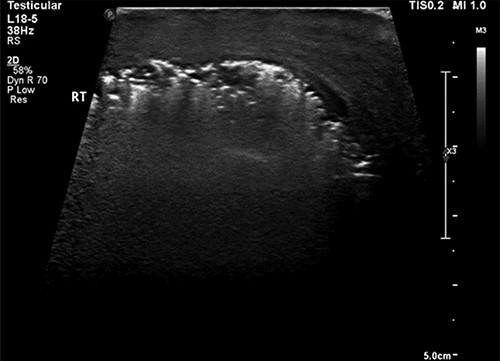

A scrotal ultrasound scan arranged within a few hours of presentation showed echogenic gas shadows within scrotal sac posing difficulty with visualization of underlying structures including testis and epididymis (Fig. 1). These findings were further corroborated by a pelvic non-contrast CT scan.

Ultrasound image of the right hemiscrotum showing gas bubbles causing acoustic shadowing and ringdown reverberation artifacts obscuring the deep tissue namely testicular parenchyma.